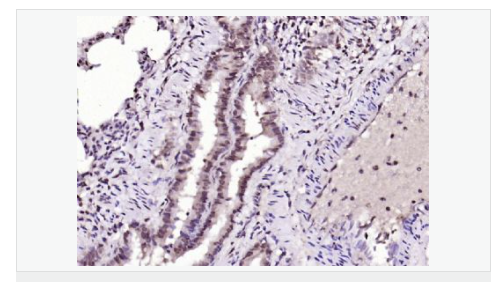

| 產品應用 | ELISA=1:5000-10000 IHC-P=1:100-500 IHC-F=1:100-500 IF=1:100-500 (石蠟切片需做抗原修復) not yet tested in other applications. optimal dilutions/concentrations should be determined by the end user. |

| 產品介紹 | The protein encoded by this gene is a member of the BTG/Tob family. This family has structurally related proteins that appear to have antiproliferative properties. This encoded protein might play a role in neurogenesis in the central nervous system. Two transcript variants encoding different isoforms have been found for this gene. [provided by RefSeq, Aug 2008]. Function: Overexpression impairs serum-induced cell cycle progression from the G0/G1 to S phase. Subunit: Interacts with KCNMA1 tetramer. There are probably 4 molecules of KCMNB1 per KCNMA1 tetramer. Subcellular Location: Membrane; Multi-pass membrane protein. Tissue Specificity: Abundantly expressed in smooth muscle. Low levels of expression in most other tissues. Within the brain, relatively high levels found in hippocampus and corpus callosum. Similarity: Belongs to the KCNMB (TC 8.A.14.1) family. KCNMB1 subfamily. SWISS: Q14201 Gene ID: 10950 Database links: Important Note: This product as supplied is intended for research use only, not for use in human, therapeutic or diagnostic applications |